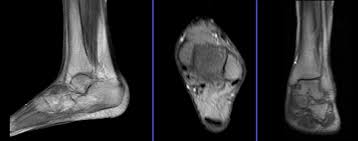

Traumatic And Non Traumatic Bone Marrow Edema In Ankle Mri A Pictorial Essay Insights Into Imaging Full Text

Traumatic And Non Traumatic Bone Marrow Edema In Ankle Mri A Pictorial Essay Insights Into Imaging Full Text from media.springernature.com

Small movements can cause distorted images and result in a longer scan. Individuals pursue this degree to become radiologist assistants, a more advanced type of radiologic technician with more responsibilities in radiological procedures and patient assessment. Depending on the severity and complexity of an injury, the ankle mri may take anywhere from about fifteen minutes to half an hour to complete. This method is used only if the person has claustrophobia, or at a large weight. What does the mri of the foot show? Ct scans can reveal more detail about the bones of the joint. An mri (magnetic resonance imaging) scans are very good at diagnosing ligament injuries and sprains and stress fractures. Moderate injuries may take between three and four weeks.

Single mri images are called slices.